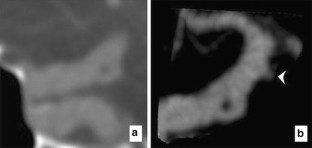

Fenestrations (segmental duplications) of the intracranial arteries are rare anomalies that have been associated with aneurysms. Fenestrations of the supraclinoid ICA are extremely rare, with only a few reported cases. We present a supraclinoid ICA fenestration, which on axial CTA images initially mimicked an aneurysm, but was correctly delineated as a fenestration on multiplanar reformatted and 3D reconstructed images. Confirmation was made with conventional angiography. To our knowledge, this represents the first time that this rare variant has been identified with cross-sectional imaging. A review of the literature including proposed embryology is provided.

Fig. 1

Fig. 2

Fig. 3

Fig. 4